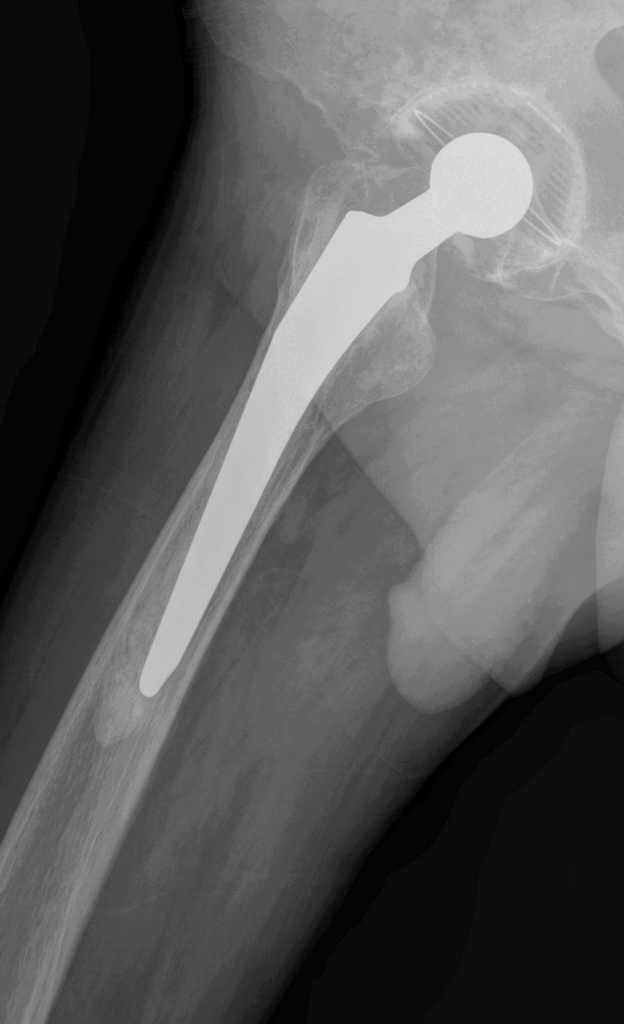

Больной М.,75л. Страдает коксартрозом. В 2005 справа и в 2007 г. слева эндопротезирование т\б суставов.

Через полгода после операции появилась боль в правой паховой области, правом бедре(средней и верхней третях)при движениях и особенно осевой нагрузке на правую ногу.

Неоднократно Р графия т\б суставов, сцинтиграфия костей скелета без четких данных,с нашей точки зрения, за нестабильность комопнентов протеза справа.

Оцените пожалуйста предстваленные Р граммы, имеются ли на них признаки нестабильности?